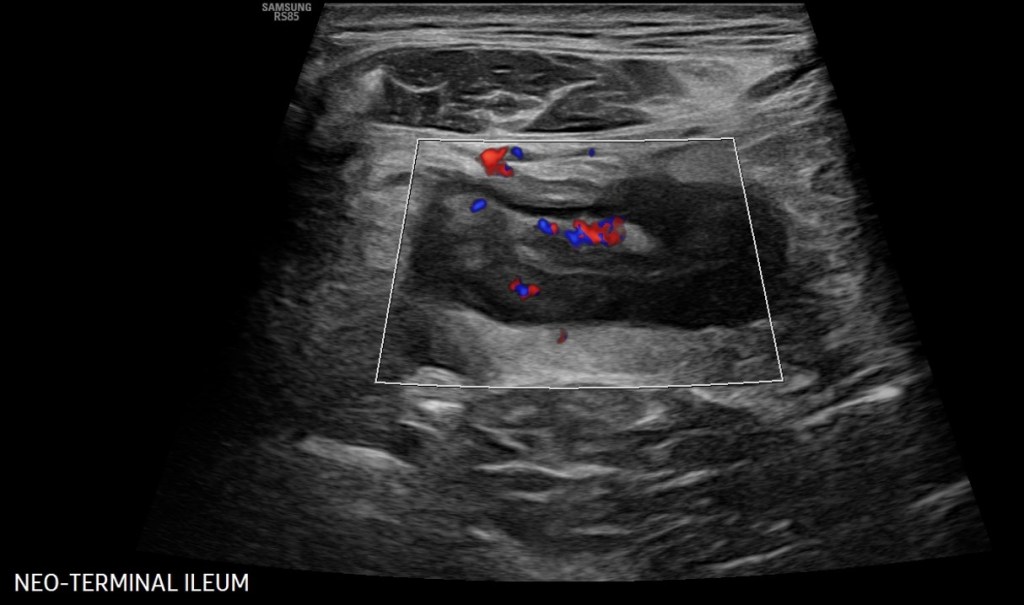

Intestinal Ultrasound (IUS) is an abdominal ultrasound performed during a routine clinic visit without preparation, fasting, or contrast to assess both the colon and the small intestine (terminal ileum most frequently) for the presence of disease activity. Probes are placed over the abdomen and the provider looks at images of the small and large bowel.

The beauty is that, unlike procedures and other image modalities available to assess disease activity of inflammatory bowel disease, IUS can be performed without any preparation or fasting,” said Dr. Chavannes. “In the setting of active disease, patients can have a thickened appearance of the wall of the bowel (termed increased bowel wall thickness) in both the small intestine and the colon, which can be detected via ultrasound.”

In addition, by using color Doppler, a feature that assesses the velocity of blood flow within and around the bowel wall, gastroenterologists can demonstrate inflammatory activity in the bowel wall. IUS can also detect IBD complications, such as fistulas, abscesses, or strictures (narrowing) of the bowel.

“Our expectation is that, with effective therapies, the aforementioned features of disease activity should improve or even disappear over subsequent clinic visits. If they do not, we now have an objective tool available in the clinic that can assist clinical decisions, such as ordering further investigations or even optimizing or changing therapy. Improvement of bowel wall thickening or decrease in color Doppler signaling is a reassuring sign that treatment is working. Lack of improvement signifies that optimization or changes in therapy should be considered,” explained Dr. Chavannes.

“Intestinal ultrasound is precise, we monitor bowel wall thickness down to the 0.1 mm. We are now able to make informed decisions with patients together, assessing their disease objectively in real-time so we can be aligned with our treatment goals. This reduces misunderstanding and may lead to better treatment adherence and improved outcomes,” said Dr. Dolinger.